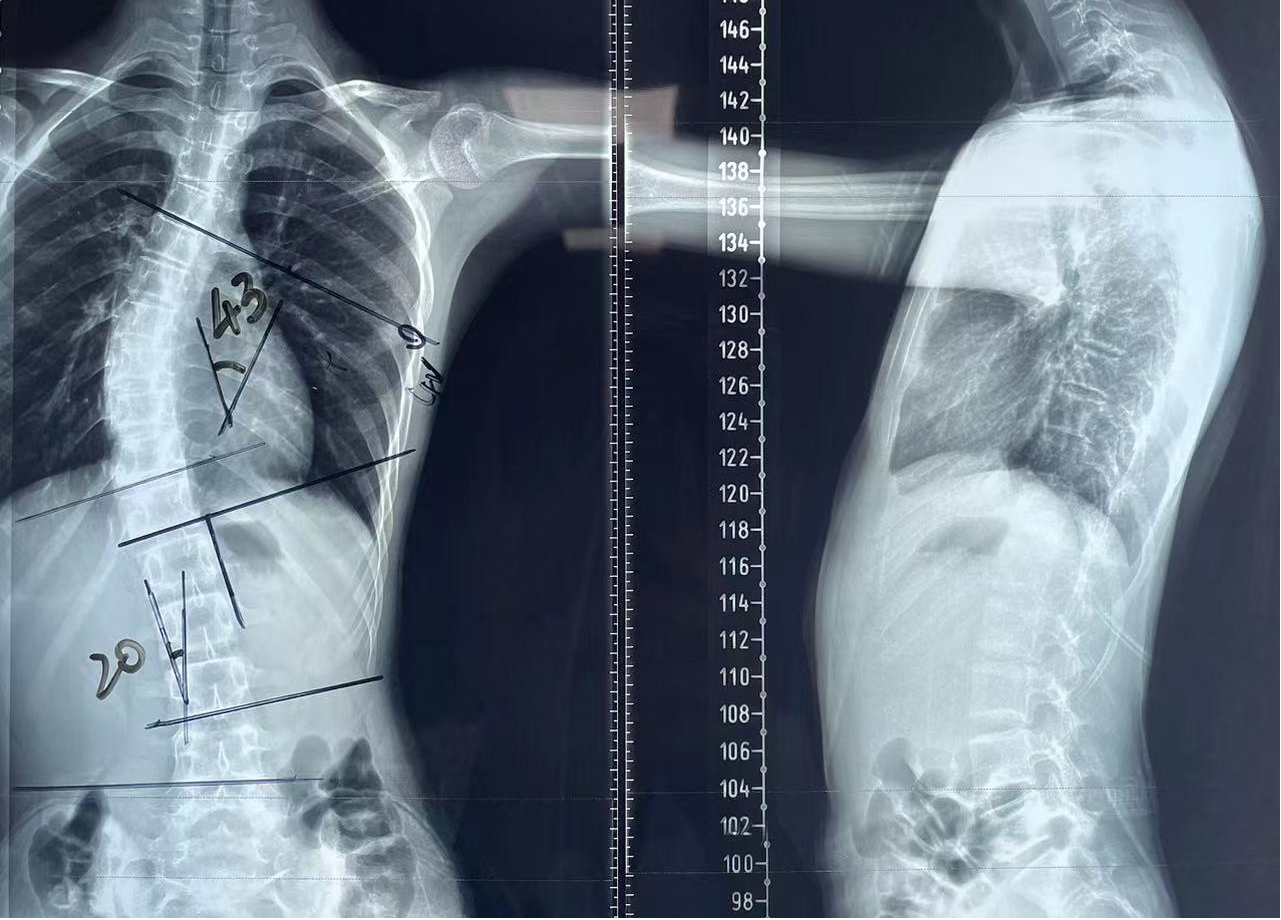

今年13岁的乐乐(化名)长期生活在内蒙古呼和浩特市,几个月前,家人发现乐乐后背双侧不等高,在当地医院就诊后,医生建议手术治疗。多方打听后,去年12月,父母带着乐乐慕名找到了我院骨科脊柱外科主任张文志教授。张文志立即为乐乐完善了相关检查,全脊柱正侧位X线片检查提示脊柱侧弯,胸椎Cobb角度43°,需要手术治疗。

▲术前影像检查提示脊柱严重侧弯

“手术很顺利,术中出血量约200ml,术后Cobb角小于5度,乐乐身高也增加了2cm。”乐乐父母一直悬着的心也放下了,术后第5天,乐乐顺利出院,迎来了他的“直立人生”。